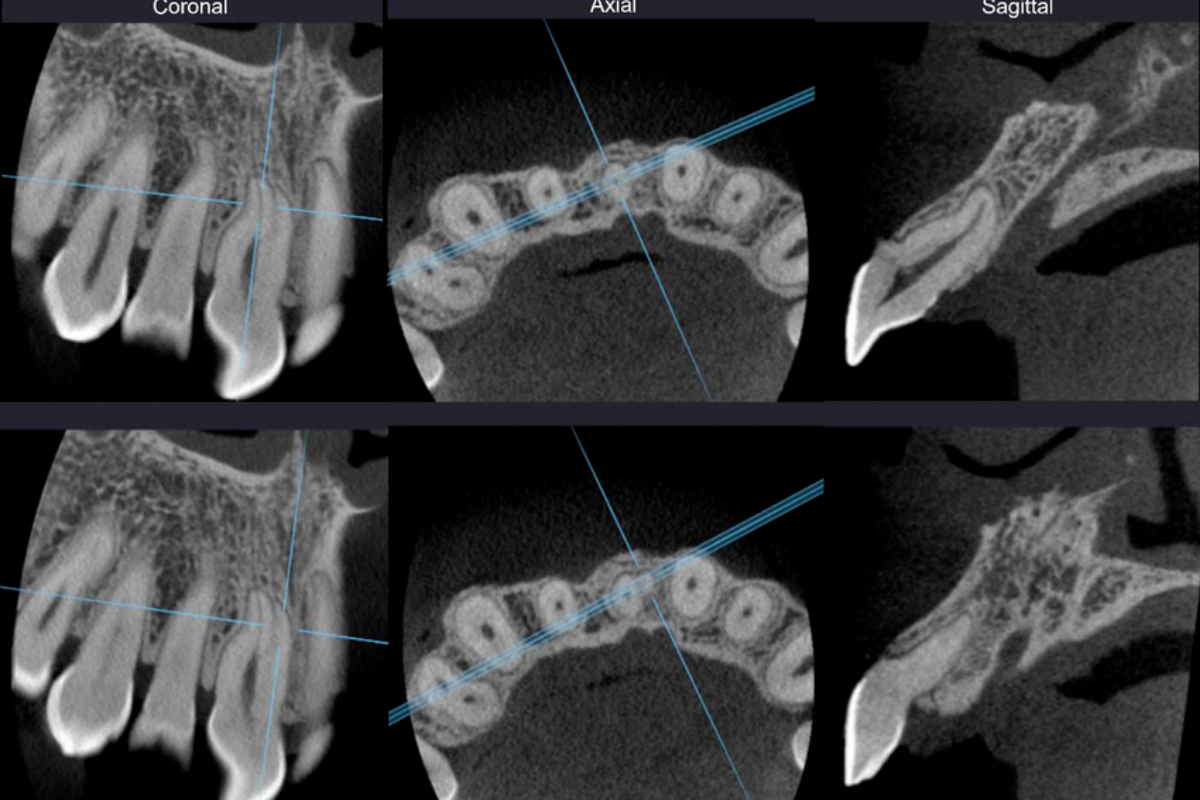

- CBCT con protocolos de dosis optimizada según indicación.

- Selección de FOV y resolución (vóxel) según objetivo clínico.

- Procesamiento para reducción de artefactos por metal cuando aplica.

- Endodoncia: alta resolución y campo pequeño cuando se requiere detalle fino.

- Visualización y navegación por cortes (en CBCT) para análisis clínico.

- En CBCT, indicar región y objetivo para ajustar FOV y resolución.

¿Realizan CBCT de alta resolución para endodoncia?

Sí. Cuando la indicación lo requiere, se puede trabajar con campo reducido y mayor detalle para evaluación fina de estructuras.